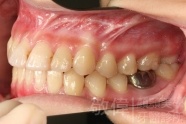

變臉矯正,原來戽斗妹跟大歪臉變成自信正妹

經由本院3D數影X光影像儀分析、與3D齒顎顏矯正技術,再配合口腔顎面正顎專科醫師施以正顎手術治療,雙方共同合作,使患者臉部外觀有很好的改善,大歪變小歪,產生了天南地北的大改變,她的人生也整個變得不一樣。

因為矯正與正顎手術的配合,使「戽斗妹」變成了「陽光正妹」,完全的改變了她的人生,在面對各種場合、與人交際都散發出自信微笑。所以,奉勸家長,如果小朋友有臉顎畸型的問題,應該考慮配合做這種簡單、安全、有效的正顎手術。

「3D齒顎顏矯正」,不止矯正您的牙齒,也會改變您的人生。「治療前」和「治療後」出社會的人生際遇一定會截然不同。